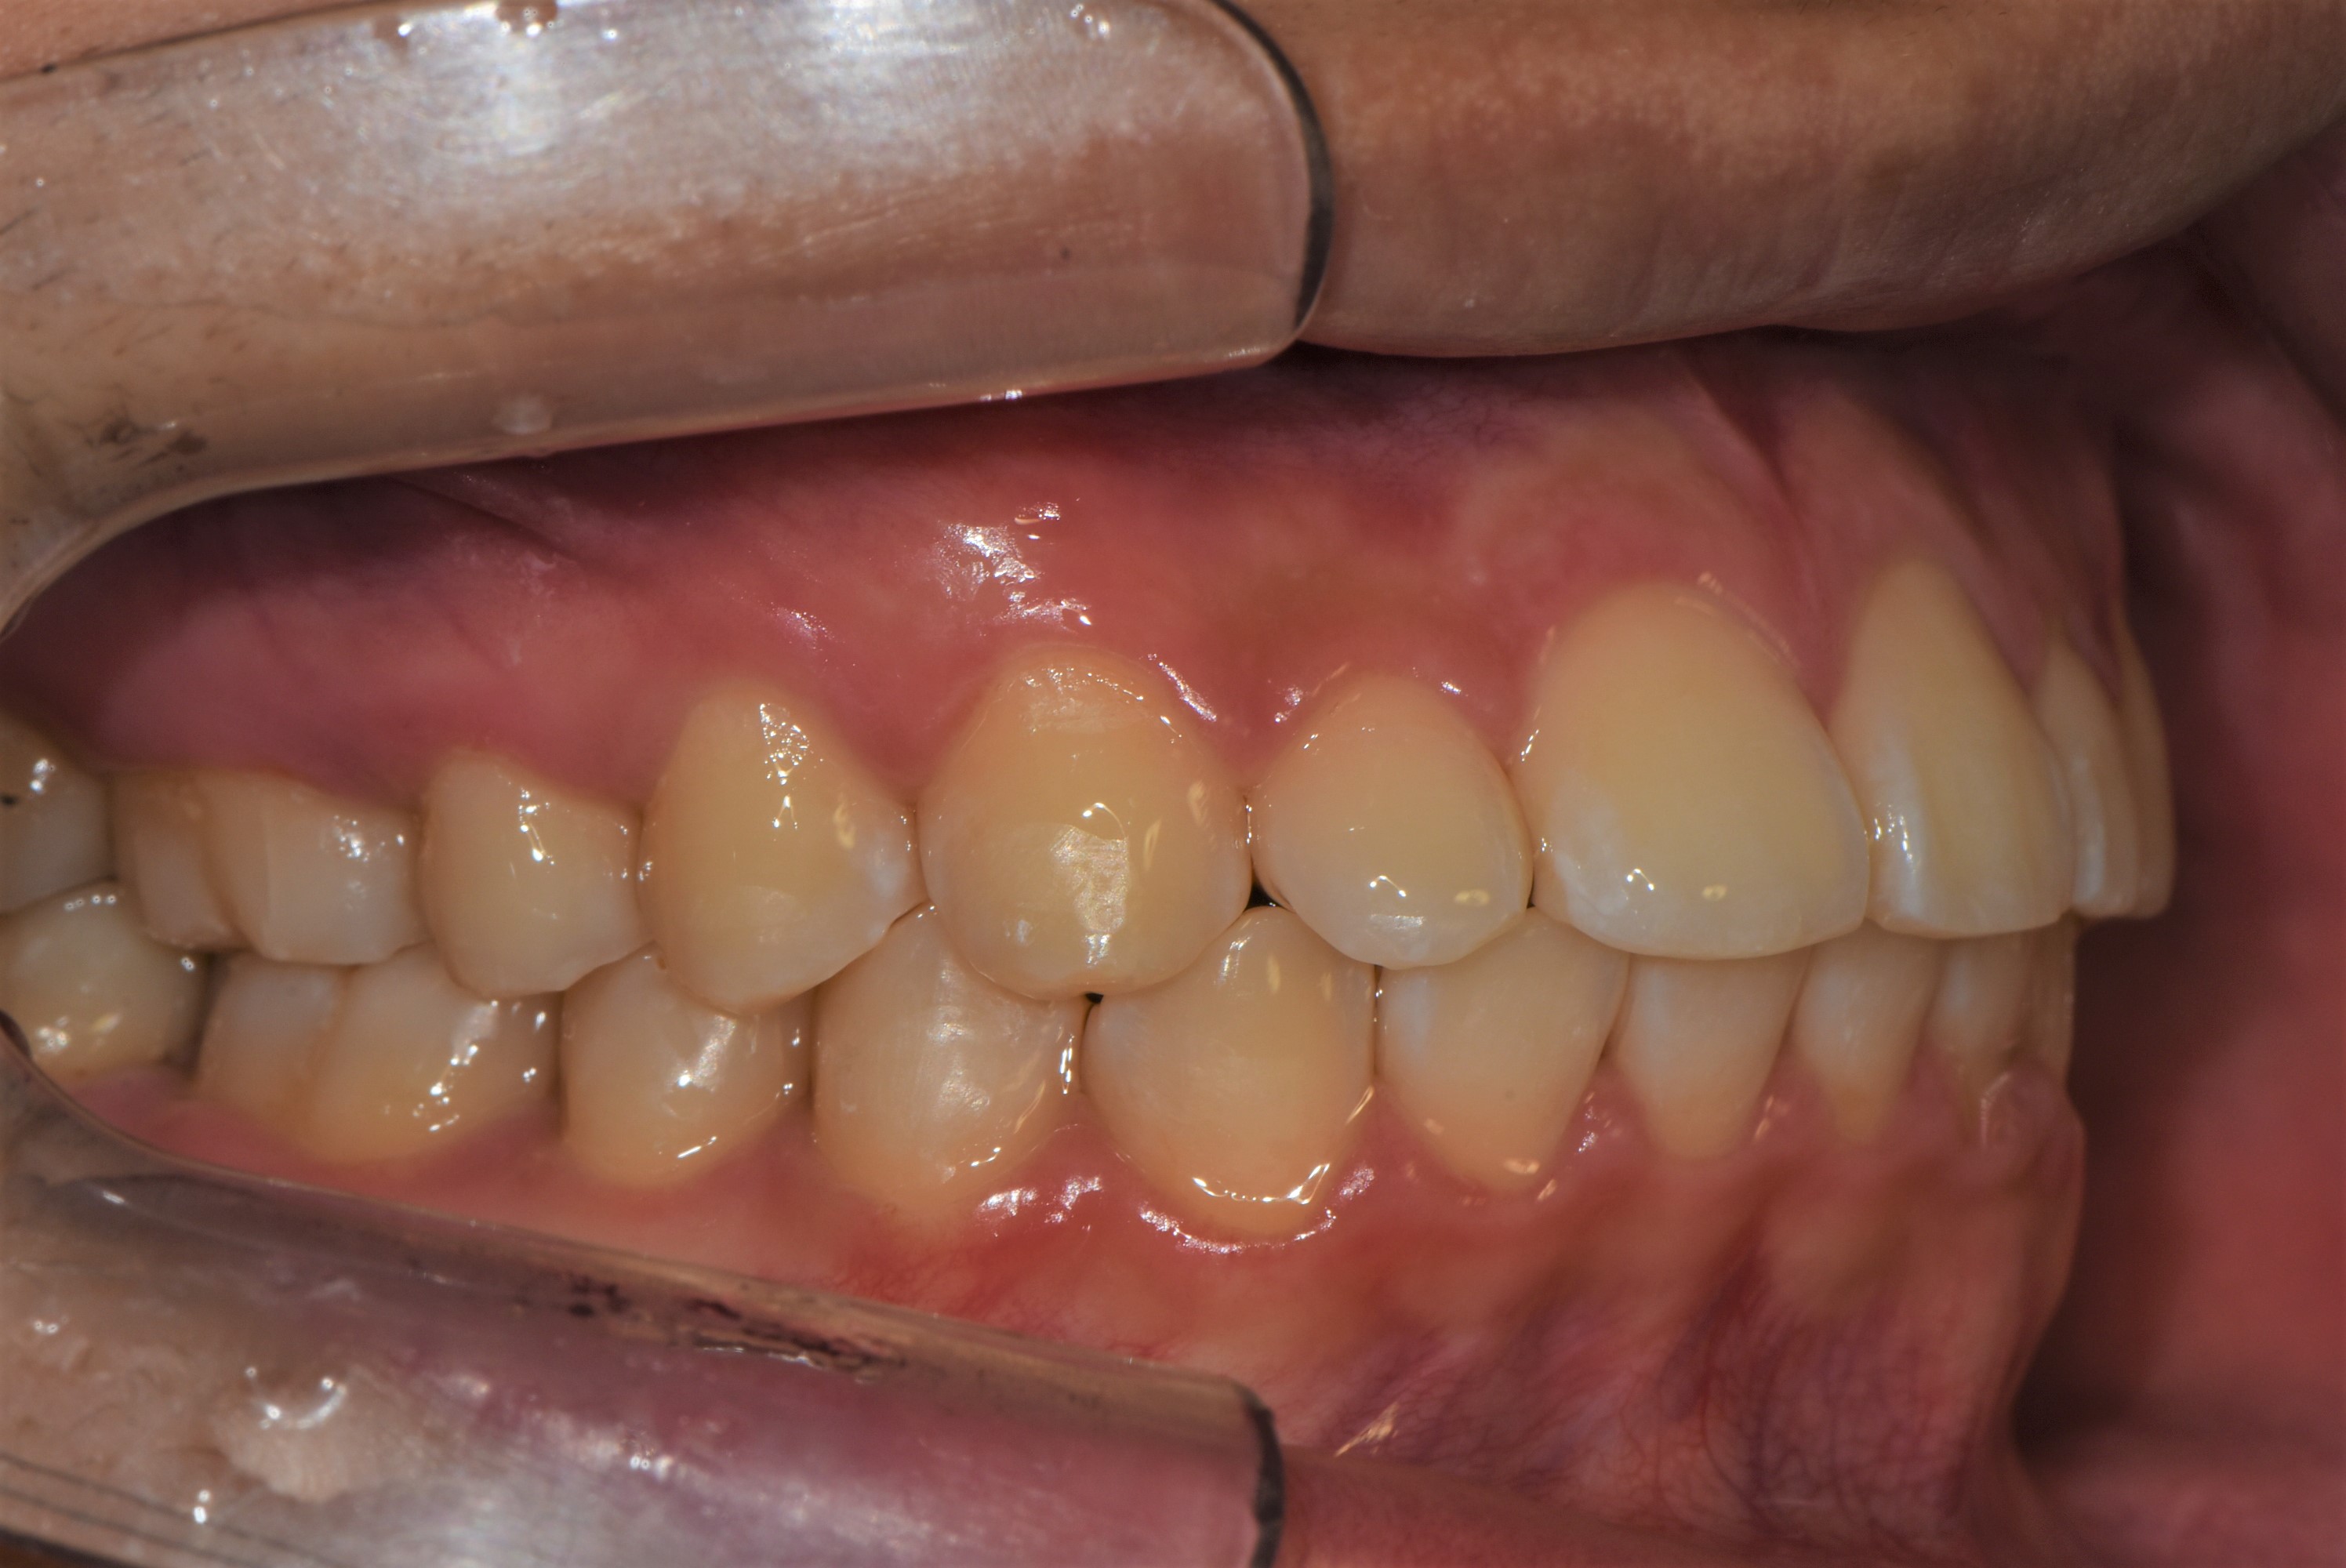

치료 후 사진입니다.